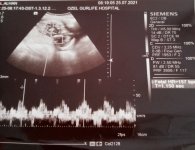

Merhaba arkadaşlar 17+3 haftalığız bugün cinsiyetimizi öğrenecektik ama bebeğim bacak arasını açmadı öğrenemedik 2 hafta sonra yine çağırdı doktor çok merak ediyorum bugün ki ultrason görüntümüz ne diyorsunuz

17+3 haftalığız bugün cinsiyetimizi öğrenecektik ama bebeğim bacak arasını açmadı öğrenemedik 2 hafta sonra yine çağırdı doktor çok merak ediyorum bugün ki ultrason görüntümüz ne diyorsunuz

Yok mu yorum yapacak🙈🥰 çok meraktayım☺️